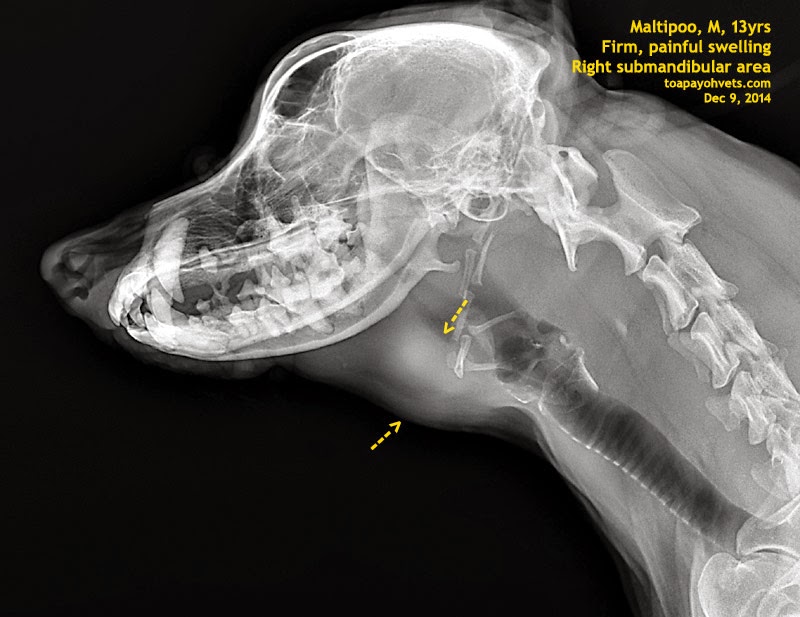

2010vets 2915. Throat X rays of the dog and cat A 14yearold Normal Throat X Ray Dog Sedation may be needed to reduce motion. The imaging anatomy web site is a basic atlas of normal imaging anatomy of domestic animals. Interactive radiographs of a dog's thorax, including left lateral, right lateral, and ventrodorsal views. Thoracic radiographs should be taken during peak inspiration. Affected dogs are at risk of pneumonia from inhaling food and liquid (aspiration pneumonia), dehydration,. Normal Throat X Ray Dog.